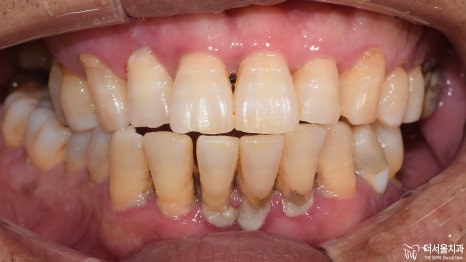

1) 정면

다량의 치석과 치은 퇴축,

치주염과 치간이개가 관찰되고 있습니다.

하악 우측 중절치는 아예 상실되어 있었습니다.

2) 측면

이쪽도 정면과 마찬가지였습니다.

구강 내에 전체적으로 번진 치주 질환 때문에

잇몸 및 치아의 상태가 좋지 않습니다.